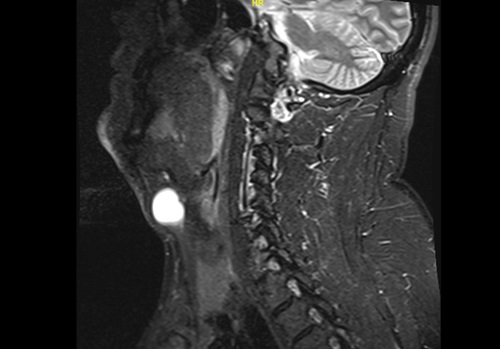

По данным МРТ от января 2023: кпереди от подъязычной кости, с распространением в правую парамедианную область выявляется кистозное образование, частично расположенное в структуре правой грудинно-подъязычной мышцы, с оттеснением правой щитоподъязычной мышцы. Форма образования неправильная, максимальные аксиальные размеры 24,5х25мм. Капсула гладкая, жидкостное содержимое неоднородное, с наличием белкового компонента.